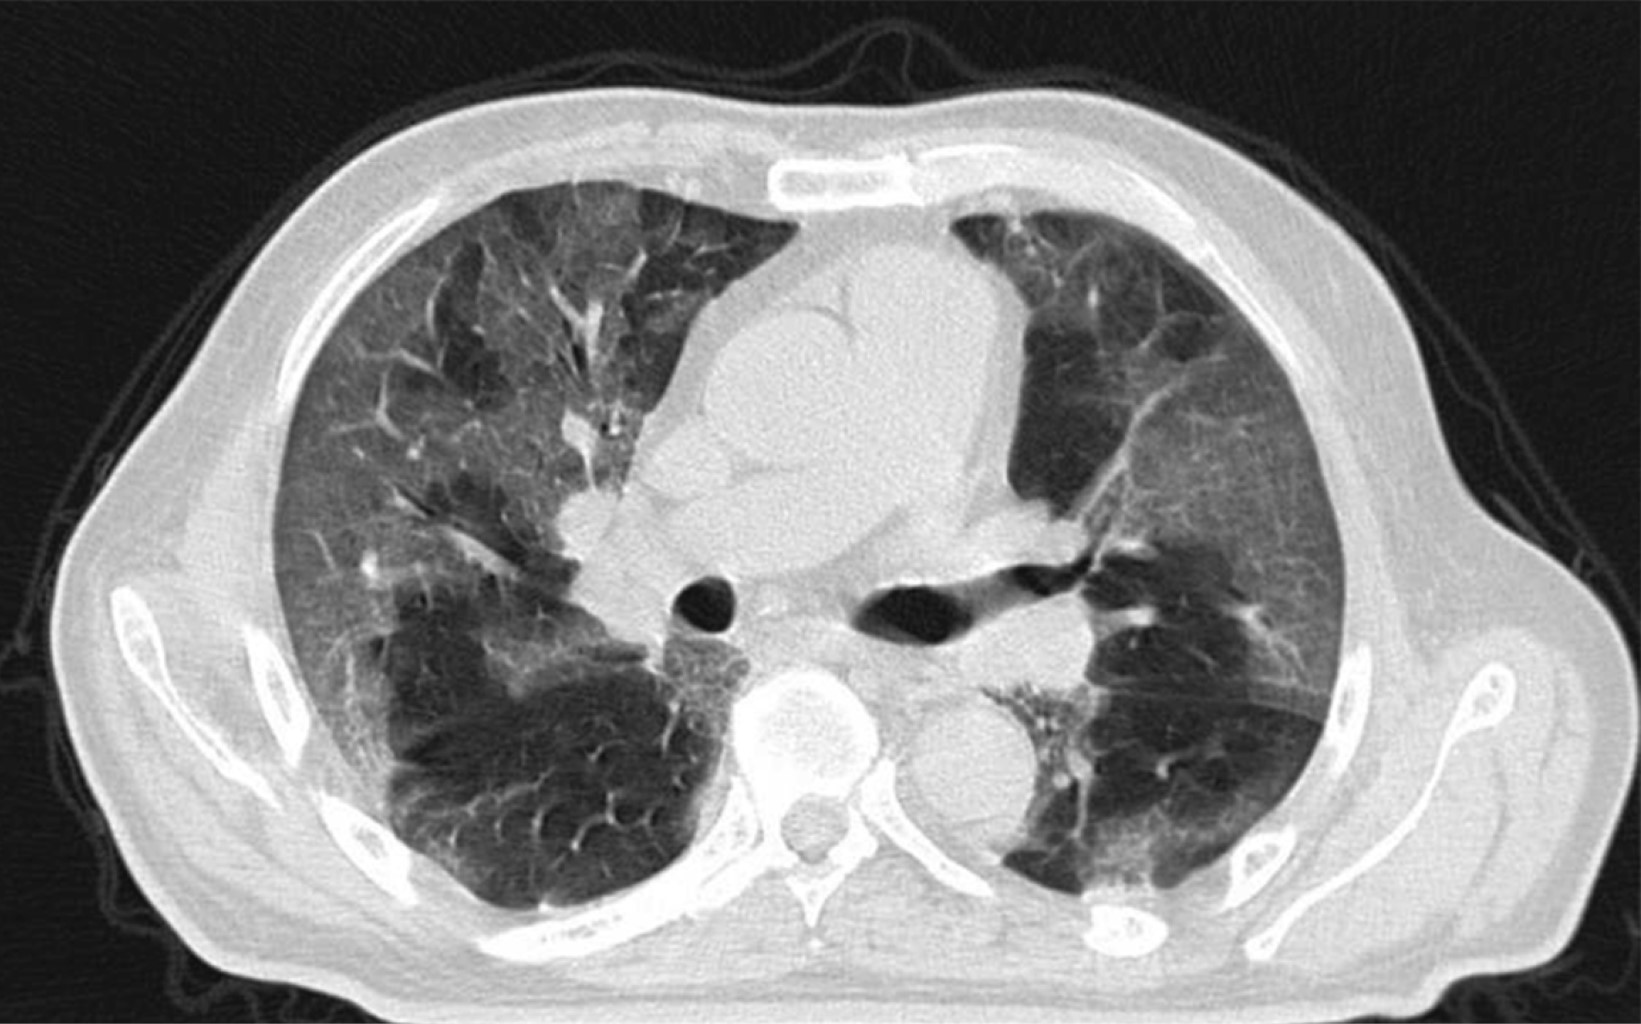

Paciente masculino de 69 años de edad con historia de diabetes mellitus tipo 2 en tratamiento con metformina y clorpropamida, hipertensión arterial en tratamiento con losartán y amlodipino. Se presenta al servicio de urgencias por mostrar cefalea, dolor torácico, tos, mialgias, artralgias y disnea de una semana de evolución. A su ingreso muestra frecuencia cardiaca 114 lpm, frecuencia respiratoria de 24 rpm, saturación de oxígeno de 80% sin apoyo de oxígeno suplementario, glucosa 587 mg/dl, leucocitos de 25,690 cel/mm3, neutrófilos 85%, linfocitos 1.2%, hemoglobina 16.3 g/dl, procalcitonina 3.78 ng/dl, gasometría arterial con pH 7.41, pCO2 21 mmHg, PO2 35 mmHg, HCO3 13 mmol/l, saturación de oxígeno 62%. Se realiza prueba rápida de antígeno para SARS-CoV-2 resultando positiva, tomografía axial computarizada (TAC) de tórax en la que se observan datos radiológicos sugestivos de infección por SARS-CoV-2 (Figura 1), se inicia manejo con oxígeno suplementario, bomba de infusión de insulina, carbapenémicos, antihipertensivos, dexametasona y profilaxis antitrombótica con enoxaparina. A las 48 horas de su ingreso continúa con choque séptico, se inician aminas vasopresoras, se realiza intubación orotraqueal y soporte con ventilación mecánica invasiva, se coloca sonda nasogástrica (SNG), la cual 24 horas posterior a su colocación reporta hematemesis acompañada de distensión abdominal, leucocitosis de 40,000 cel/mm3, se realiza TAC abdominopélvica simple, la cual revela neumatosis gástrica y neumoperitoneo (Figura 2), se efectúa laparotomía exploradora urgente encontrando necrosis de la curvatura mayor del estómago, se lleva a acabo gastrectomía vertical con engrapadora GIA cartuchos morados de 45 y 60 mm (Figura 3), se refuerza línea de grapeo con sutura continua prolene 00, se coloca sonda de yeyunostomía de alimentación a 60 cm del ángulo de Treitz y se dejan drenajes tipo Saratoga. A las 24 horas postoperatorias paciente reporta estabilidad hemodinámica y se suspenden aminas vasopresoras, se inicia nutrición enteral con dieta elemental. El quinto día postquirúrgico muestra adecuada tolerancia a dieta enteral por yeyunostomía, se realiza prueba con azul de metileno por SNG sin evidencia de fugas y descenso de leucocitos a 24,000 cel/mm3. Se recaba resultado de histopatología, el cual revela necrosis panmural asociada a trombosis arterial secundaria a microorganismos compatibles con Mucor sp., por lo que se inicia manejo con anfotericina B (Figuras 4 y 5). En el seguimiento muestra buena evolución, se realiza TAC abdominopélvica con contraste por SNG, la cual descarta fugas y colecciones intraabdominales y se corrobora integridad de la pared gástrica, se retiran drenajes y se da alta de cirugía general el día nueve postquirúrgico continuando manejo a cargo del servicio de medicina interna. Durante los siguientes días de hospitalización, el paciente presenta deterioro cardiovascular y pulmonar, se toma urocultivo, el cual evidencia crecimiento de Candida tropicalis, se realiza TAC de cráneo, tórax y abdominopélvica con contraste oral (Figuras 6 y 7), continúa sin evidencia de fugas a nivel abdominal, se descarta mucormicosis rinocerebral y pulmonar, se reporta probable neumonía bacteriana sobreañadida y neumopatía intersticial secundaria a COVID-19, persiste deterioro clínico y choque refractario, el paciente fallece a 29 días de su ingreso.

Figura 7